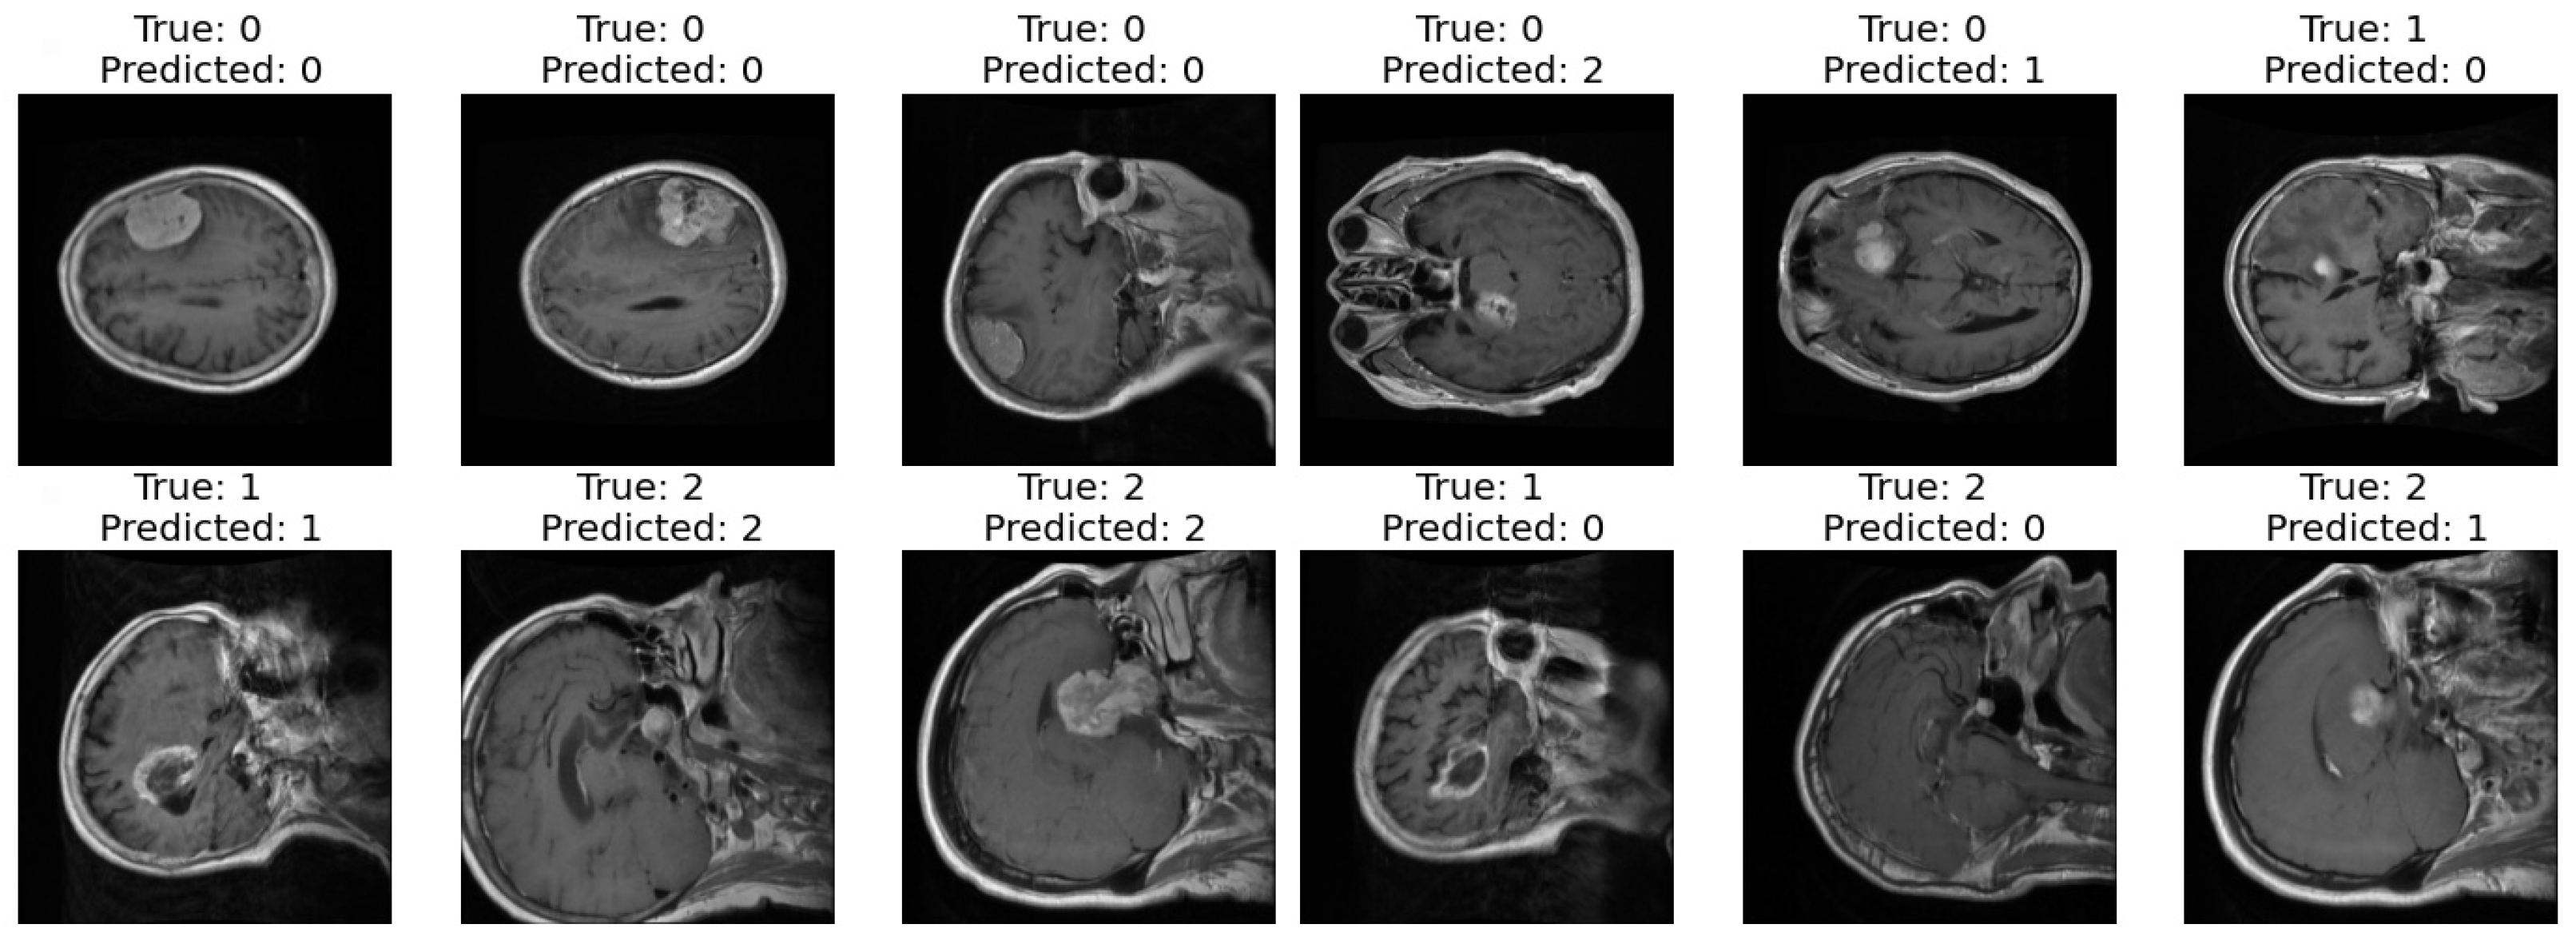

3.2. First Dataset (Classification Task)